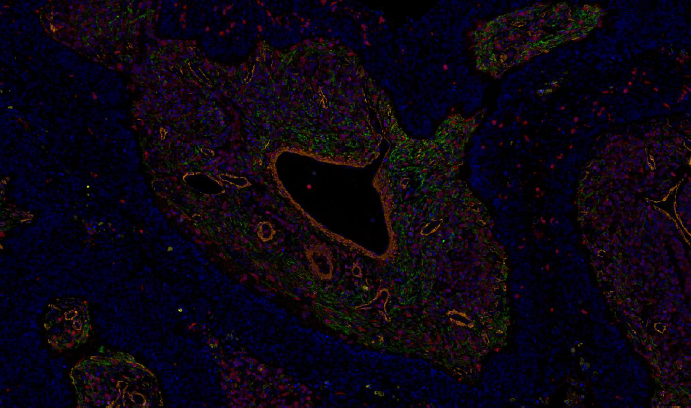

Absin mIHC实验服务结果展示

七色肺癌组织肿瘤免疫微环境THBS2,CD19,CD8,FOXP3,CD68,CD56

五色肺癌组织肿瘤免疫微环境THBS2,FAP,S100A4,αSMA